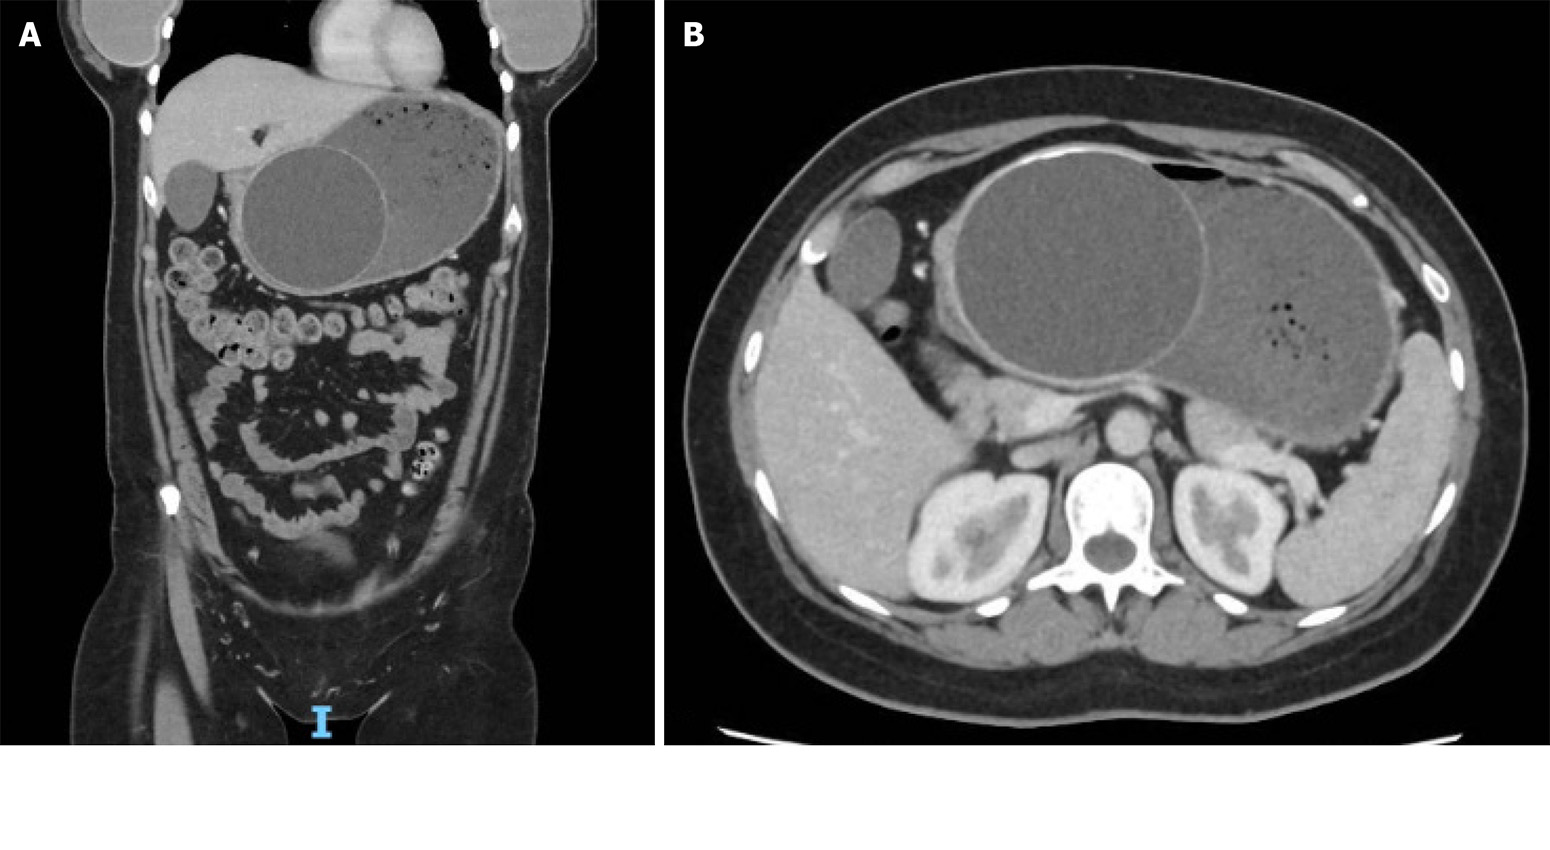

- Small bowel ulcers and bleeding: An overlooked yet critical ... 2025-10-11